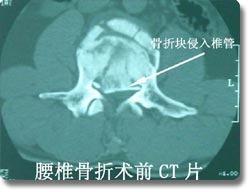

各种类型脊柱创伤的外科手术

脊柱外科是该科的主要临床特色, 也是该科近年来发展的重点。在七十年代初就在国内率先开展了颈椎前路手术,大大拓展了新桥医院骨科脊柱手术治疗的范围,在全国享有较高的知名度。随后又积极开展了脊柱脊髓损伤的临床治疗和基础实验研究, 目前已治疗患者1000余例,其优良的治疗效果和精谌的手术技巧深得同行好评,使脊柱骨折复位成功率和截瘫的恢复率得到显著改善和提高。